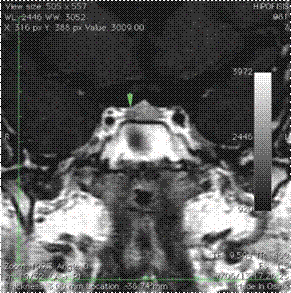

Estudios de imágenes: edad ósea de 9 años y 6 meses. La RMN en silla turca dinámica (con equipo de 3,0 Teslas) mostró una lesión de 4 mm hipocaptante (Figura 2).